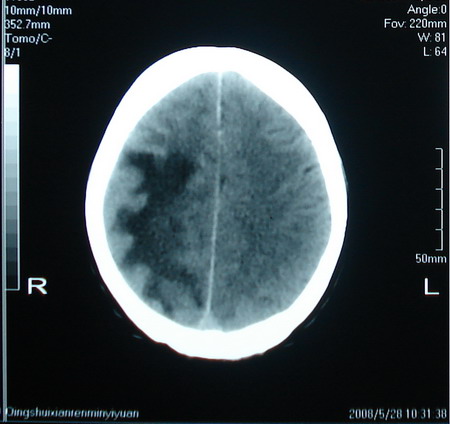

标题: CT13794:M63Y,头颅CT平扫 [打印本页]

标题: CT13794:M63Y,头颅CT平扫

男,63岁,头痛,呕吐,意识模糊一周。无发烧及感染史。

小肿瘤大水肿,考虑转移瘤

脑肿瘤 1 室管膜瘤 2 转移瘤

考虑为:胶质瘤可能性大,不排除转移瘤。建议:行进一步检查。

支持右侧丘脑恶性胶质母细胞瘤可能性大,建议增强进一步检查。